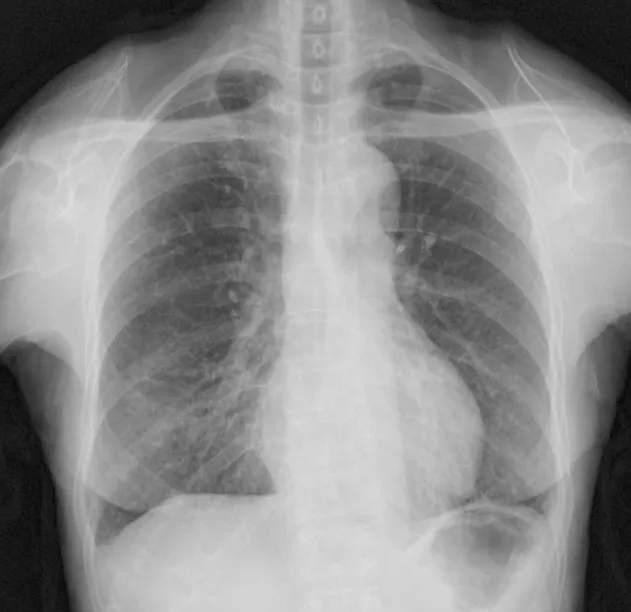

胸部CT示两下肺弥漫分布细胞粟粒样小结节影。

DAB的胸片表现包括弥漫性小结节影和非特异性间质浸润,实变相对少见,这是吸入性肺炎的常见表现。高分辨率CT扫描显示弥漫性小叶中心性结节,呈现树芽征,这与其他弥漫性细支气管疾病相似,如弥漫性泛细支气管炎(DPB)、支原体肺炎,人类嗜T淋巴病毒1型感染,变态反应性支气管肺曲霉菌病,分枝杆菌感染,滤泡性细支气管炎,囊性纤维化。